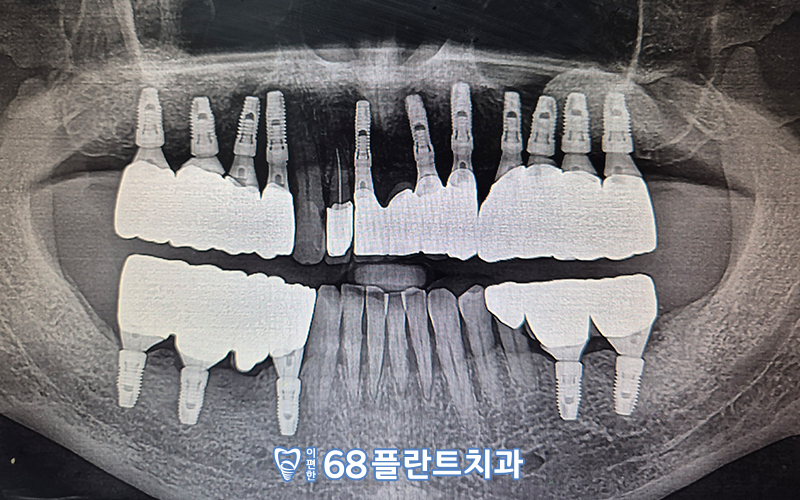

철산동치과

이편한68플란트치과에서의

치료 후 파노라마 사진입니다! 🙂

뼈가 많이 녹아 흔들리고 예후가 좋지 않았던

치아들을 발치하였고,

기존 상실되어 있던 부위와 더불어

임플란트 치료를

안정적으로 마무리해준 모습이랍니다.

계획한 위치 및 방향대로

잘 식립이 되었고,

환.자분께서 편안하게 저작하실 수 있도록

교합부분에서도 신경 써

보철 제작을 도와드렸습니다.